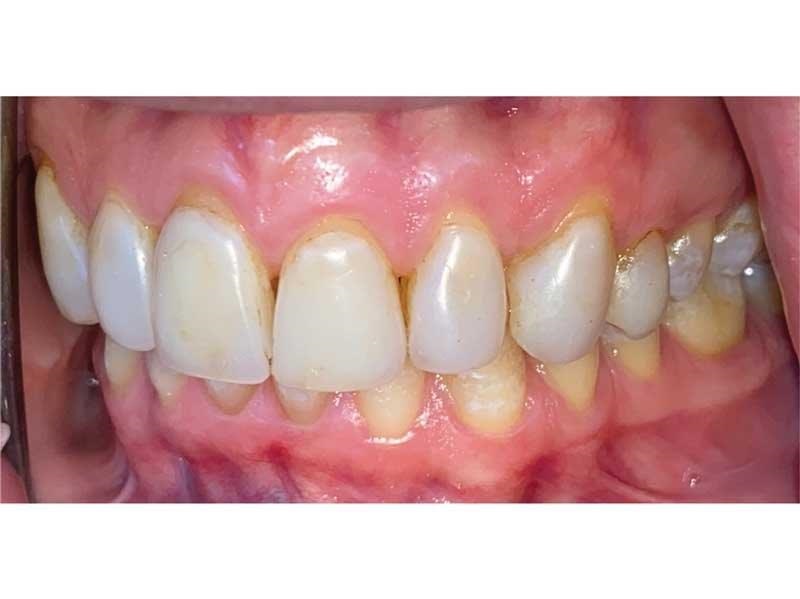

Meet Lorraine, who came into my office to “redo her bonding.” Lorraine had some upper anterior teeth done years ago with resin, which now was dull, stained and breaking down (Figs. 1–3). She had an amount of money in mind that she thought it would cost. She was very wrong.

Fig. 1

Fig. 2

Fig. 3